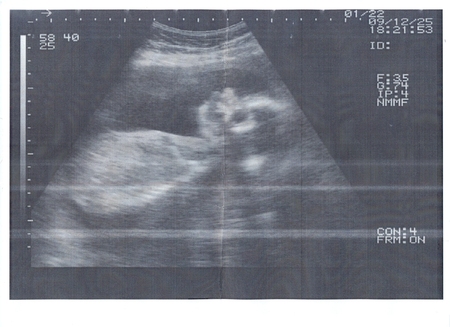

УЗИ 25.12.2009 г.

В пятницу ходили на УЗИ, наконец то нам сказали пол нашего малыша..У нас будет сына))) Муж прямо в кабинете от счастья запрыгал...Только вышли из кабинета я даже телефон достать еще не успела он уже половину норода обзвонил с радостной новостью. Но самле главное у нас все в норме растем хорошо никаких отклонении нет

Вот он мои шладенькии хоречик: